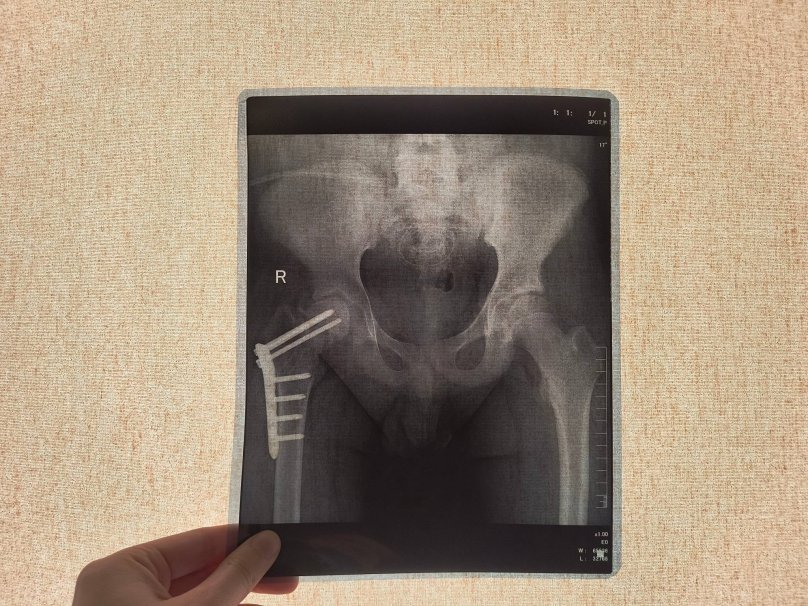

Спершу лікарі підозрювали параліч, однак обстеження показало перелом шийки стегна. Кістка зламалася без жодного удару — через критичну крихкість, викликану порушенням мінерального обміну на тлі хвороби нирок.

Після операції у Дніпрі нирки хлопця відмовили, і він опинився на гемодіалізі. Водночас через слабкість кістки встановлені гвинти змістилися і почали руйнувати кульшовий суглоб.

Під час операції спеціалісти видалили гвинти, виконали репозицію уламків і зафіксували їх пластиною. Далі застосували інноваційну технологію — введення стовбурових клітин у місце перелому для стимуляції зрощення.